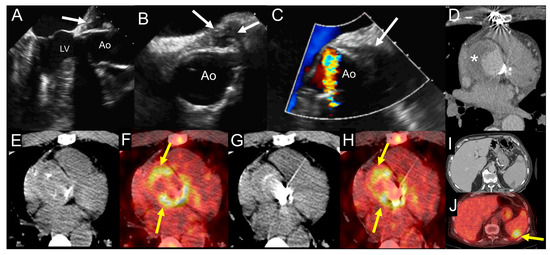

6.4. When to Ask for Nuclear Imaging

- Pizzi, M.N.; Roque, A.; Fernandez-Hidalgo, N.; Cuellar-Calabria, H.; Ferreira-Gonzalez, I.; Gonzalez-Alujas, M.T.; Oristrell, G.; Gracia-Sanchez, L.; Gonzalez, J.J.; Rodriguez-Palomares, J.; et al. Improving the diagnosis of infective endocarditis in prosthetic valves and intracardiac devices with 18F-fluordeoxyglucose positron emission tomography/computed tomography angiography: Initial results at an infective endocarditis referral center. Circulation 2015, 132, 1113–1126. [Google Scholar] [CrossRef] [PubMed]

- Roque, A.; Pizzi, M.N.; Cuellar-Calabria, H.; Aguade-Bruix, S. 18F-FDG-PET/CT angiography for the diagnosis of infective endocarditis. Curr. Cardiol. Rep. 2017, 19, 15. [Google Scholar] [CrossRef] [PubMed]

- Tanis, W.; Scholtens, A.; Habets, J.; Brink, R.B.V.D.; Van Herwerden, L.A.; Chamuleau, S.A.; Budde, R.P. CT Angiography and 18F-FDG-PET Fusion Imaging for Prosthetic Heart Valve Endocarditis. JACC Cardiovasc. Imaging 2013, 6, 1008–1013. [Google Scholar] [CrossRef]

- Swart, L.; Gomes, A.; Scholtens, A.; Sinha, B.; Tanis, W.; Lam, M.G.; Van Der Vlugt, M.J.; Streukens, S.A.F.; Aarntzen, E.H.; Bucerius, J.; et al. Improving the diagnostic performance of 18 F-Fluorodeoxyglucose Positron-Emission tomography/computed tomography in prosthetic heart valve endocarditis. Circulation 2018, 138, 1412–1427. [Google Scholar] [CrossRef] [PubMed]